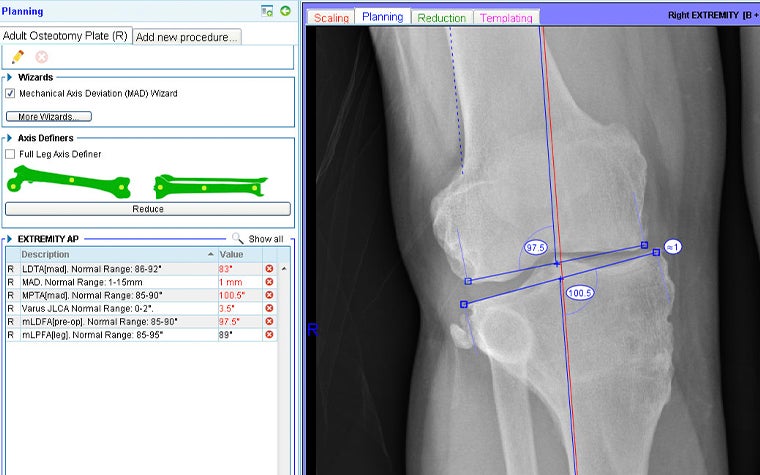

With the AP long-leg X-ray loaded into the OrthoView application, the surgeon used the Mechanical Axis Deviation (MAD) Wizard from the Limb Deformity Correction (LDC) Module.

This confirmed that the knee joint line convergence angle was outside of normal range. Specifically, using the nomenclature developed by Paley et al., the mLDFA (mechanical Lateral Distal Femoral Angle) and MPTA (Medial Proximal Tibial Angle) were 7.5 degrees and 10 degrees outside of normal range, respectively.

All values out of range are highlighted in red in figure 2.